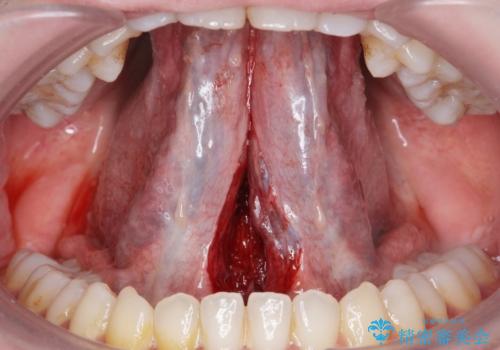

- 滑舌が悪いとの事で来院。

ラ行が言いにくいとの事でしたので舌小帯の形成術を行い、舌の可動域を広げました。

- 舌小帯切除術 3.3万円費用は治療当時の料金となります